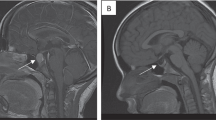

Universal newborn screening for congenital hypothyroidism is practiced in many countries [2]. Screening protocols vary by region but generally begin with measurement of TSH and/or T4 in a dried blood spot collected from each infant within a few days after birth. Prompt diagnosis and treatment of congenital hypothyroidism is critical for ensuring optimal developmental outcome, so any abnormal newborn screen result should prompt immediate confirmation of TSH and free T4 concentrations in a serum sample. TSH elevation, with or without low free T4, indicates the presence of congenital primary hypothyroidism. Central hypothyroidism may be present if free T4 is low and TSH is normal or low; however, this condition can be difficult to diagnose, particularly in ill or preterm infants (see below). If central hypothyroidism is confirmed, further evaluation should include assessment for other pituitary hormone deficits and brain imaging that includes the hypothalamus and pituitary. Examination of the optic discs by a pediatric ophthalmologist may reveal evidence of associated septo-optic dysplasia.